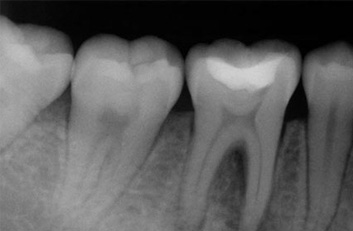

Una endodoncia es un tratamiento que se realiza como última recurso antes de realizar la extracción de una pieza dental. Cuando la caries es muy profunda puede tocar tejidos dentarios llegando al nivel del nervio “pulpa”, esto sucede cuando una caries no fue tratada a tiempo y se perciben molestias al tomar alimentos fríos o calientes, en cuyo caso lo más probable es que sea esto lo que esté sucediendo, el dolor puede llegar a tornarse insoportable y es eso lo que se pretende evitar con una endodoncia el dolor y la posibilidad de una infección con la consiguiente pérdida de una pieza dental. Una endodoncia no duele, se siente igual que un relleno ordinario. La endodoncia es inevitable si lo que se desea es conservar la pieza dental, sin tratamiento, el tejido que rodea el diente se infectaría, por lo que no se debe empastar con una obturación normal, puesto que si lo hacemos, la pieza seguiría molestando, la sensibilidad seria mayor, la infección se diseminará a través del sistema de conductos radiculares del diente produciendo un absceso e irremediablemente la pieza tendría que ser extraída.

Durante un procedimiento de conducto radicular, o endodoncia el nervio y la pulpa se eliminan y el interior del diente se limpia, se empasta la raíz con los materiales correspondientes y se procede a la reconstrucción de la corona dental, todo éste tratamiento se realiza habiendo aplicado anestesia local en la zona afectada, la misma anestesia que se utiliza para un simple empaste o una extracción.

La endodoncia le da más tiempo de vida útil a su pieza dental, en Dental Evolution Cancún le recomendamos evitar la extracción realizándose este procedimiento que garantizamos será sin dolor, gracias a la tecnología de vanguardia con la que contamos, instrumental rotatorio, sistema de ultrasonido, y a nuestra “radiografía digital” la cual juega un papel crucial en el procedimiento de endodoncia, además de que usted estará atendido con la calidez, calidad humana y profesionalismo que caracteriza a nuestro experto equipo de dentistas especializados que le apoyaran en todo momento.